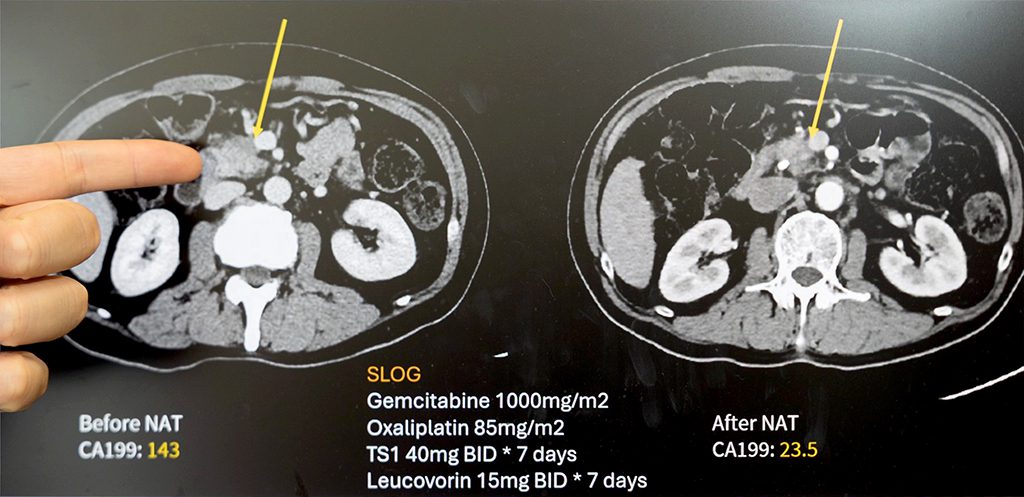

【記者吳玉惠/臺南報導】 62歲的王先生出現體重減輕與黃疸症狀,經檢查確診為胰臟癌。影像顯示腫瘤已侵犯門靜脈,屬於「邊界可切除」階段。過去此類病人往往難以直接接受手術,預後也較差。經成大醫院外科團隊多專科評估後,王先生接受「術前化學治療(Neoadjuvant Chemotherapy, NAC)」合併「擴大胰臟切除手術(Extended Pancreatectomy, EP)」。歷經四個月化療,腫瘤明顯縮小,順利完成合併血管重建的胰十二指腸切除術。術後追蹤兩年,病人恢復良好、生活如常。

廖亭凱醫師分析成大醫院2011至2022年間共405位接受胰臟癌手術的病人,並分為早期(2011-2017)與後期(2018-2022)兩個時期比較。研究結果顯示,術前化療使用率由22%提高至75%,擴大切除手術比例也由31%上升至58%,成功讓更多晚期病人轉化為可切除族群。整體中位存活期由19.2個月延長至30.3個月,死亡風險下降49%,疾病惡化風險則降低37%。此外,擴大切除的手術死亡率也由10.4%降至2.1%,突顯團隊在高難度手術與照護方面的成熟經驗。